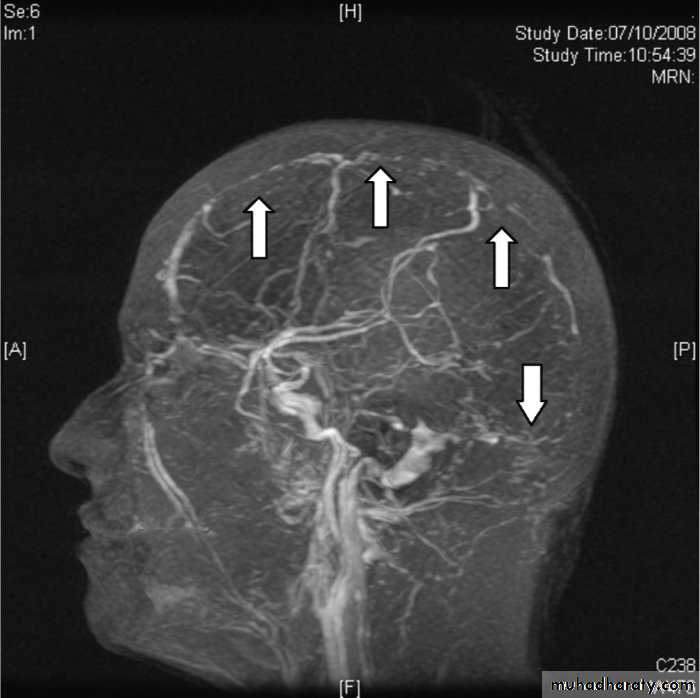

CT angiograph or MRA (magnatic resonance angiography ) in case of AVM (arteriovenois maformation ) suspension.

four-vessel cerebral arteriography,CT angiography and Magnatic resonance angiography my be used to detect aneurysm and AVM .

MR venography demonstrates a filling defect in the affected vessel.